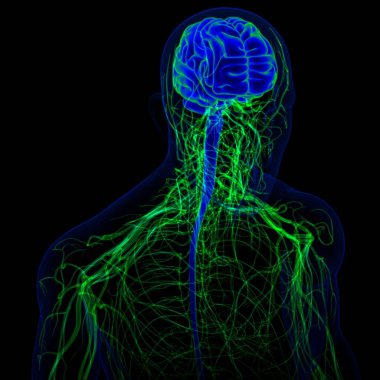

Tıbbi Konsept için sinir sistemi anatomisi olan 3D İnsan Beyni

MaviGrafikselresimlemeŞeffafİnsanSağlıkBaşıİlaçerkekkordonüç boyutlubiyolojikHücregövdeHastalıkİstihbaratİçeridebiyolojiBilimSistemAcıorgzihinomurgaelektronİşaretgörüntü oluşturmaanatomiomurilikbeyinMerkezGerginNörolojimikroskobikBeyin fırtınasıSıhhiyeanatomikSinirbeyincikcerebra3d oluşturmaüzerine siyahsinir hücresiBenzer İçerikler